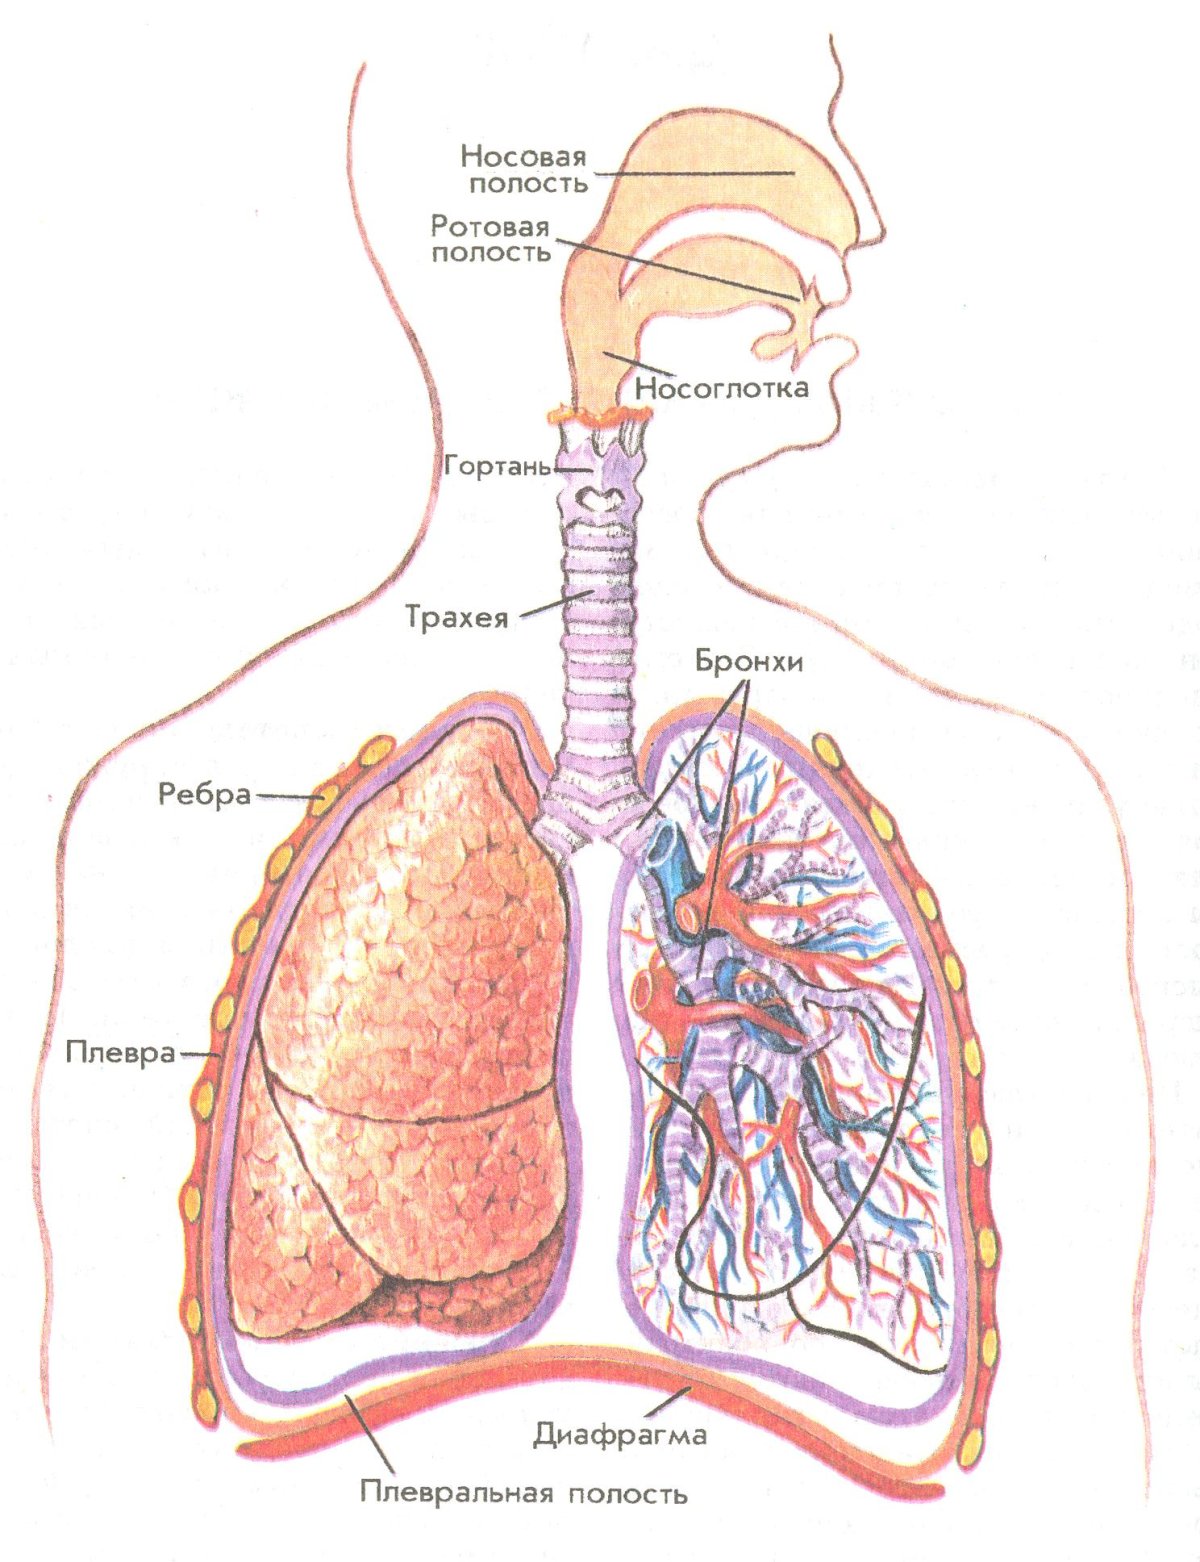

Здоровье дыхательной системы: бронхи и легкие